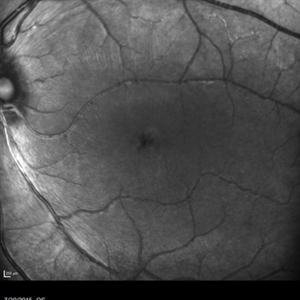

Retinal Dystrophy of 24-Year-Old Male/ IR OD

Fluorescein angiography of a 24-year-old male. Juvenile retinoschisis on OCT. FA shows outer retinal staining. Could be associated with Goldman Farve Syndrome.

Photographer: Zach Dupureur OCT-C

Imaging device: Heidelberg Spectralis

Condition/keywords: Goldmann-Favre Syndrome, juvenile retinoschisis, retinal dystrophy